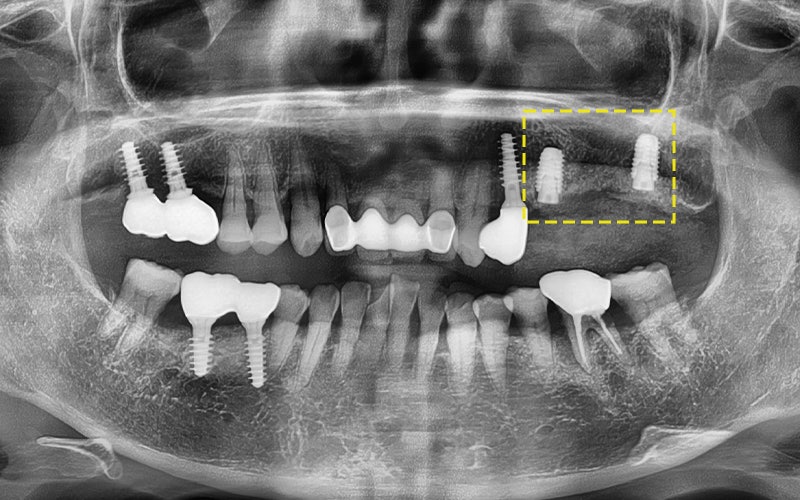

🔷 임플란트가 부러졌던 환자분 이야기

“심은 지 3년도 안 됐는데

임플란트가 부러졌어요…”

위 환자분께서는

타 치과에서 임플란트를 심은 지

약 3년밖에 되지 않았다고 하셨는데요.

임플란트가 물리적으로

파절(나사체 부러짐) 되었고,

잇몸 염증까지 발생해

주변 치아까지 영향을 주는 심각한 상황이었습니다.

위 사진은 실제로 제거한 임플란트인데요.

나사체가 금속 피로로 인해 뚝 부러졌고,

머리 부분 근처에는 치석과 염증이

가득한것을 확인할 수 있습니다.

주변 잇몸뼈가 녹아내려

결국 옆 치아까지 발치 하였고

결국 임플란트를 다시 심어야 했고,

전체적인 재건이 필요했습니다.